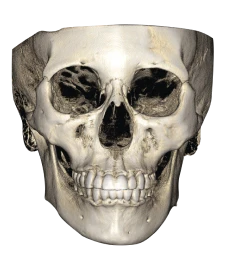

Один снимок — все детали

RAYSCAN 18х16 может с лёгкостью и точностью охватить обширную область анатомии. Его замечательная способность захватывать как назион, так и глабеллу, область от подбородка до лба, всё это в одном сканировании высотой 16 см действительно впечатляет.

Познакомьтесь с технологией получения изображений с использованием полноразмерного датчика от RAY. Этот метод не только позволяет получать объёмные изображения без сшивания, но и сводит к минимуму радиационное облучение в целях безопасности пациентов.

Ортодонтия & ЧЛХ

- Оценка роста

- Анализ симметрии лица

- План ортодонтического лечения

- Анализ дыхательных путей и ВНЧС

- Моделирование ортогнатической хирургии